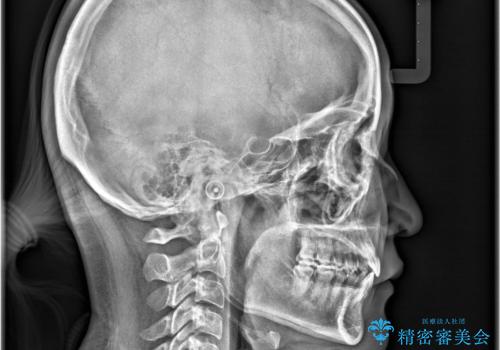

- 「下の前歯が斜めになっている」を主訴に来院された患者様です。

下顎前歯に叢生があり、右上2は反対咬合の状態でした。

昔から食いしばりがあるのを患者様が自覚されており、そのせいか口が開けにくいことも悩まれていました。

抜歯は行わずインビザラインで治療を行いました。